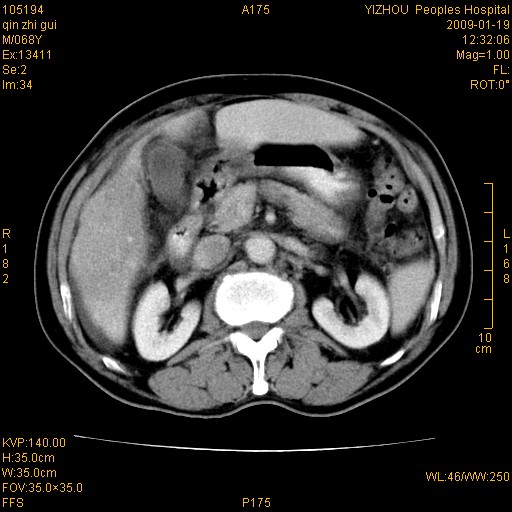

以下是引用随光逐影在2009-1-21 16:11:00的发言:[br]1)考虑肝右叶肝癌并肝静脉及门静脉瘤栓形成。2)肝硬化,少量腹水。3)胆囊炎。4)右侧少量胸腔积液。

病灶外缘凹凸不平,平扫低密度,增强动脉期有强化,门脉早显,静脉期及延期呈延迟强化,结合病史考虑右肝前叶巨块型肝癌可能性大,强化表现不除外胆管细胞癌